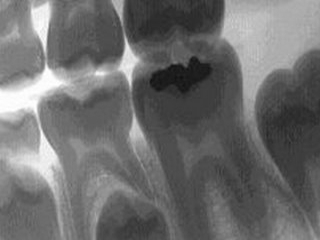

Hon fortsatte att rota och försöka få dit den där jäkla röntgenprylen. Efter ett tag tog hon en bild och konstaterade att det krävdes rotfyllning och brygga. Jag kunde dock få en provisorisk lagning för 1000:- tills jag skulle laga den på riktigt. Jag tackade nej och hoppades att hon skulle haja att jag hajade att hon ville tjäna pengar. Om ni hajar alltså?

När jag några veckor senare skulle jag laga tanden konstaterade den riktiga tandläkaren att sprickan gick ända ner i roten och att käkbenet också hade en spricka. Tanden gick inte att rädda, den måste opereras bort. Jag fick en provisorisk plastfyllning i den urborrade tanden och en ny tid för operation. Den provisoriska lagningen ingick nu och allt kostade 550 kronor. Undrar vart den där akuttandläkaren fick 1000 spänn ifrån?